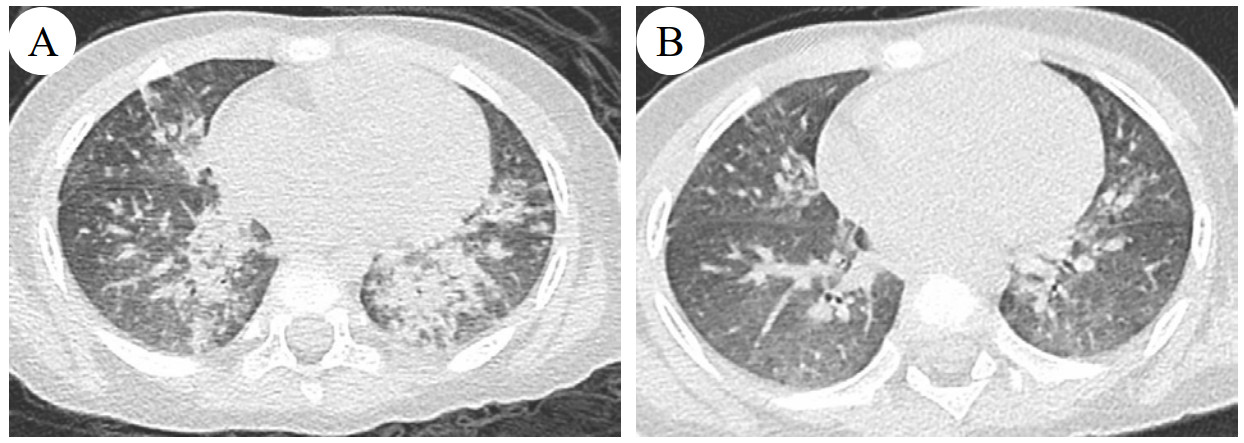

患者入院后给予洗胃,洗出少量暗红色液体,伴间断恶心,禁食留置胃管。伴间断发热,最高39 ℃,呼吸急促,阵发性咳嗽,肺部闻及粗湿啰音,血气分析提示低氧血症,面罩吸氧(5 L/min)状态下血氧饱和度维持不佳,改为持续气道正压通气(continuous positive airway pressure, CPAP)无创呼吸机辅助通气,结合相关辅助检查,考虑肺部感染,给予哌拉西林他唑巴坦1.125 g静滴每8 h一次(Q8H),14 d后停用;氨溴索注射液7.5 mg静滴Q12H,14 d后停用;布地奈德混悬液1 mg联合硫酸特布他林2.5 mg雾化吸入Q6H治疗,12 d后减量为Q12H,14 d后停用;应用20%甘露醇注射液40 mL静滴Q8H,3 d后减量为Q12H,4 d后减量为QD,6 d后停用;甲泼尼龙26 mg静滴QD,5 d后停用;奥美拉唑10 mg静滴QD,3 d后停用,磷酸肌酸钠0.5 g静滴QD,12 d后停用;余对症支持治疗。经治疗未再惊厥发作,住院第2天恶心好转,经口喂养可耐受,CPAP辅助呼吸4 d后停用,呼吸急促症状好转,自主呼吸状态下血氧饱和度监测正常;住院第8天复查视频脑电图未见异常;住院第10天体温正常,咳嗽好转,肺部CT提示双肺多发斑片状密度增高影,边缘模糊,段及段以上支气管通畅(图 2A)。住院15 d临床症状恢复出院。出院后2周复诊,患者已无临床症状,复查肺部CT提示双肺支气管血管束增粗伴透光度欠均,小斑片影及索条影较前好转(图 2B)。

| 注:A为患者病程第10天,B为患者病程第30天 图 2 患者胸部CT影像学变化 |